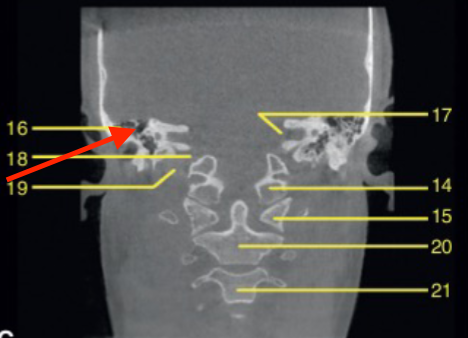

coronal

what plane

posterior of maxillary sinus

where is this slice

mental foramen (at premolar region)

identify the structure

molar region

where is this slice located

mandibular canal/inferior alveolar canal

what is the ARROW pointing to